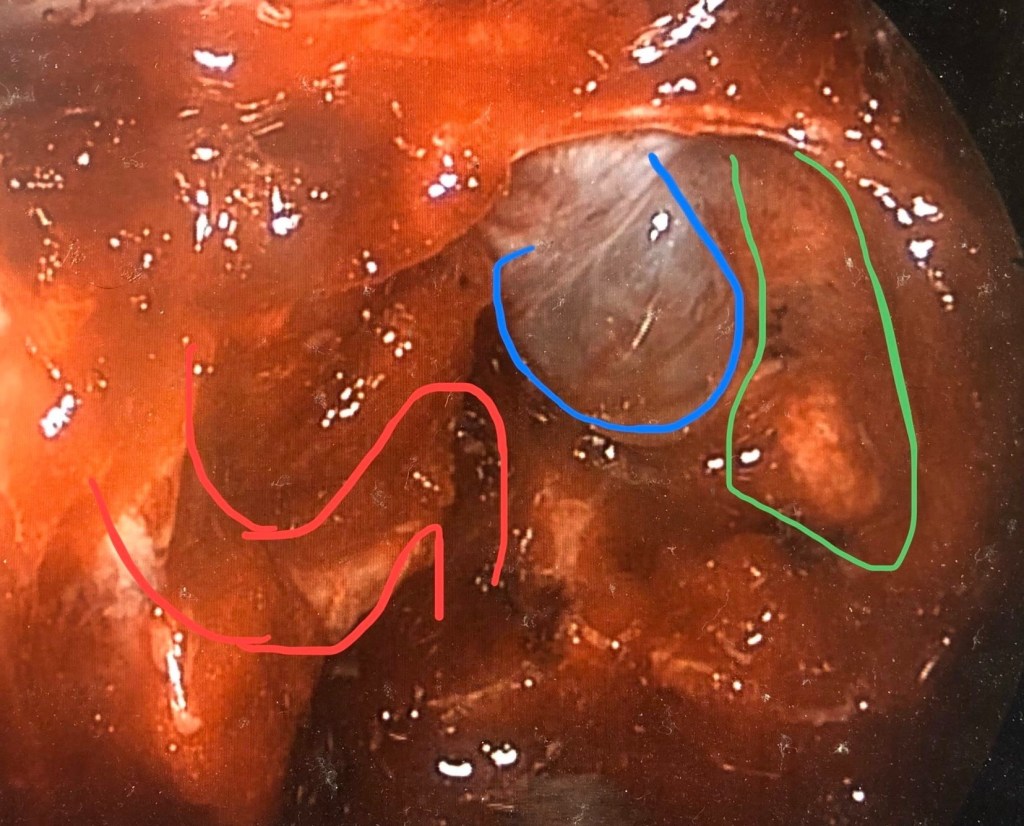

ผู้ป่วยรายนี้ได้รับการทำผ่าตัดโดยการส่องกล้องผ่านทางโพรงจมูกและนำเนื้องอกออกจนหมดโดยเก็บเนื้อต่อมใต้สมองส่วนอื่นไว้ได้ หลังผ่าตัดผู้ป่วยระดับฮอร์โมนต่ำตั้งแต่วันแรกๆ ระดับความดันกลับเป็นปกติสามารถหยุดยาความดันได้ทุกตัว น้ำหนักตัวลดจาก 67 เป็น 41 กิโลกรัม ไม่มีการขาดฮอร์โมนอื่นเพิ่มเติม 4ปีหลังผ่าตัดผู้ป่วยมีชีวิตเป็นปกติและไม่ต้องอาศัยการรักษาอื่นร่วมด้วยเลย